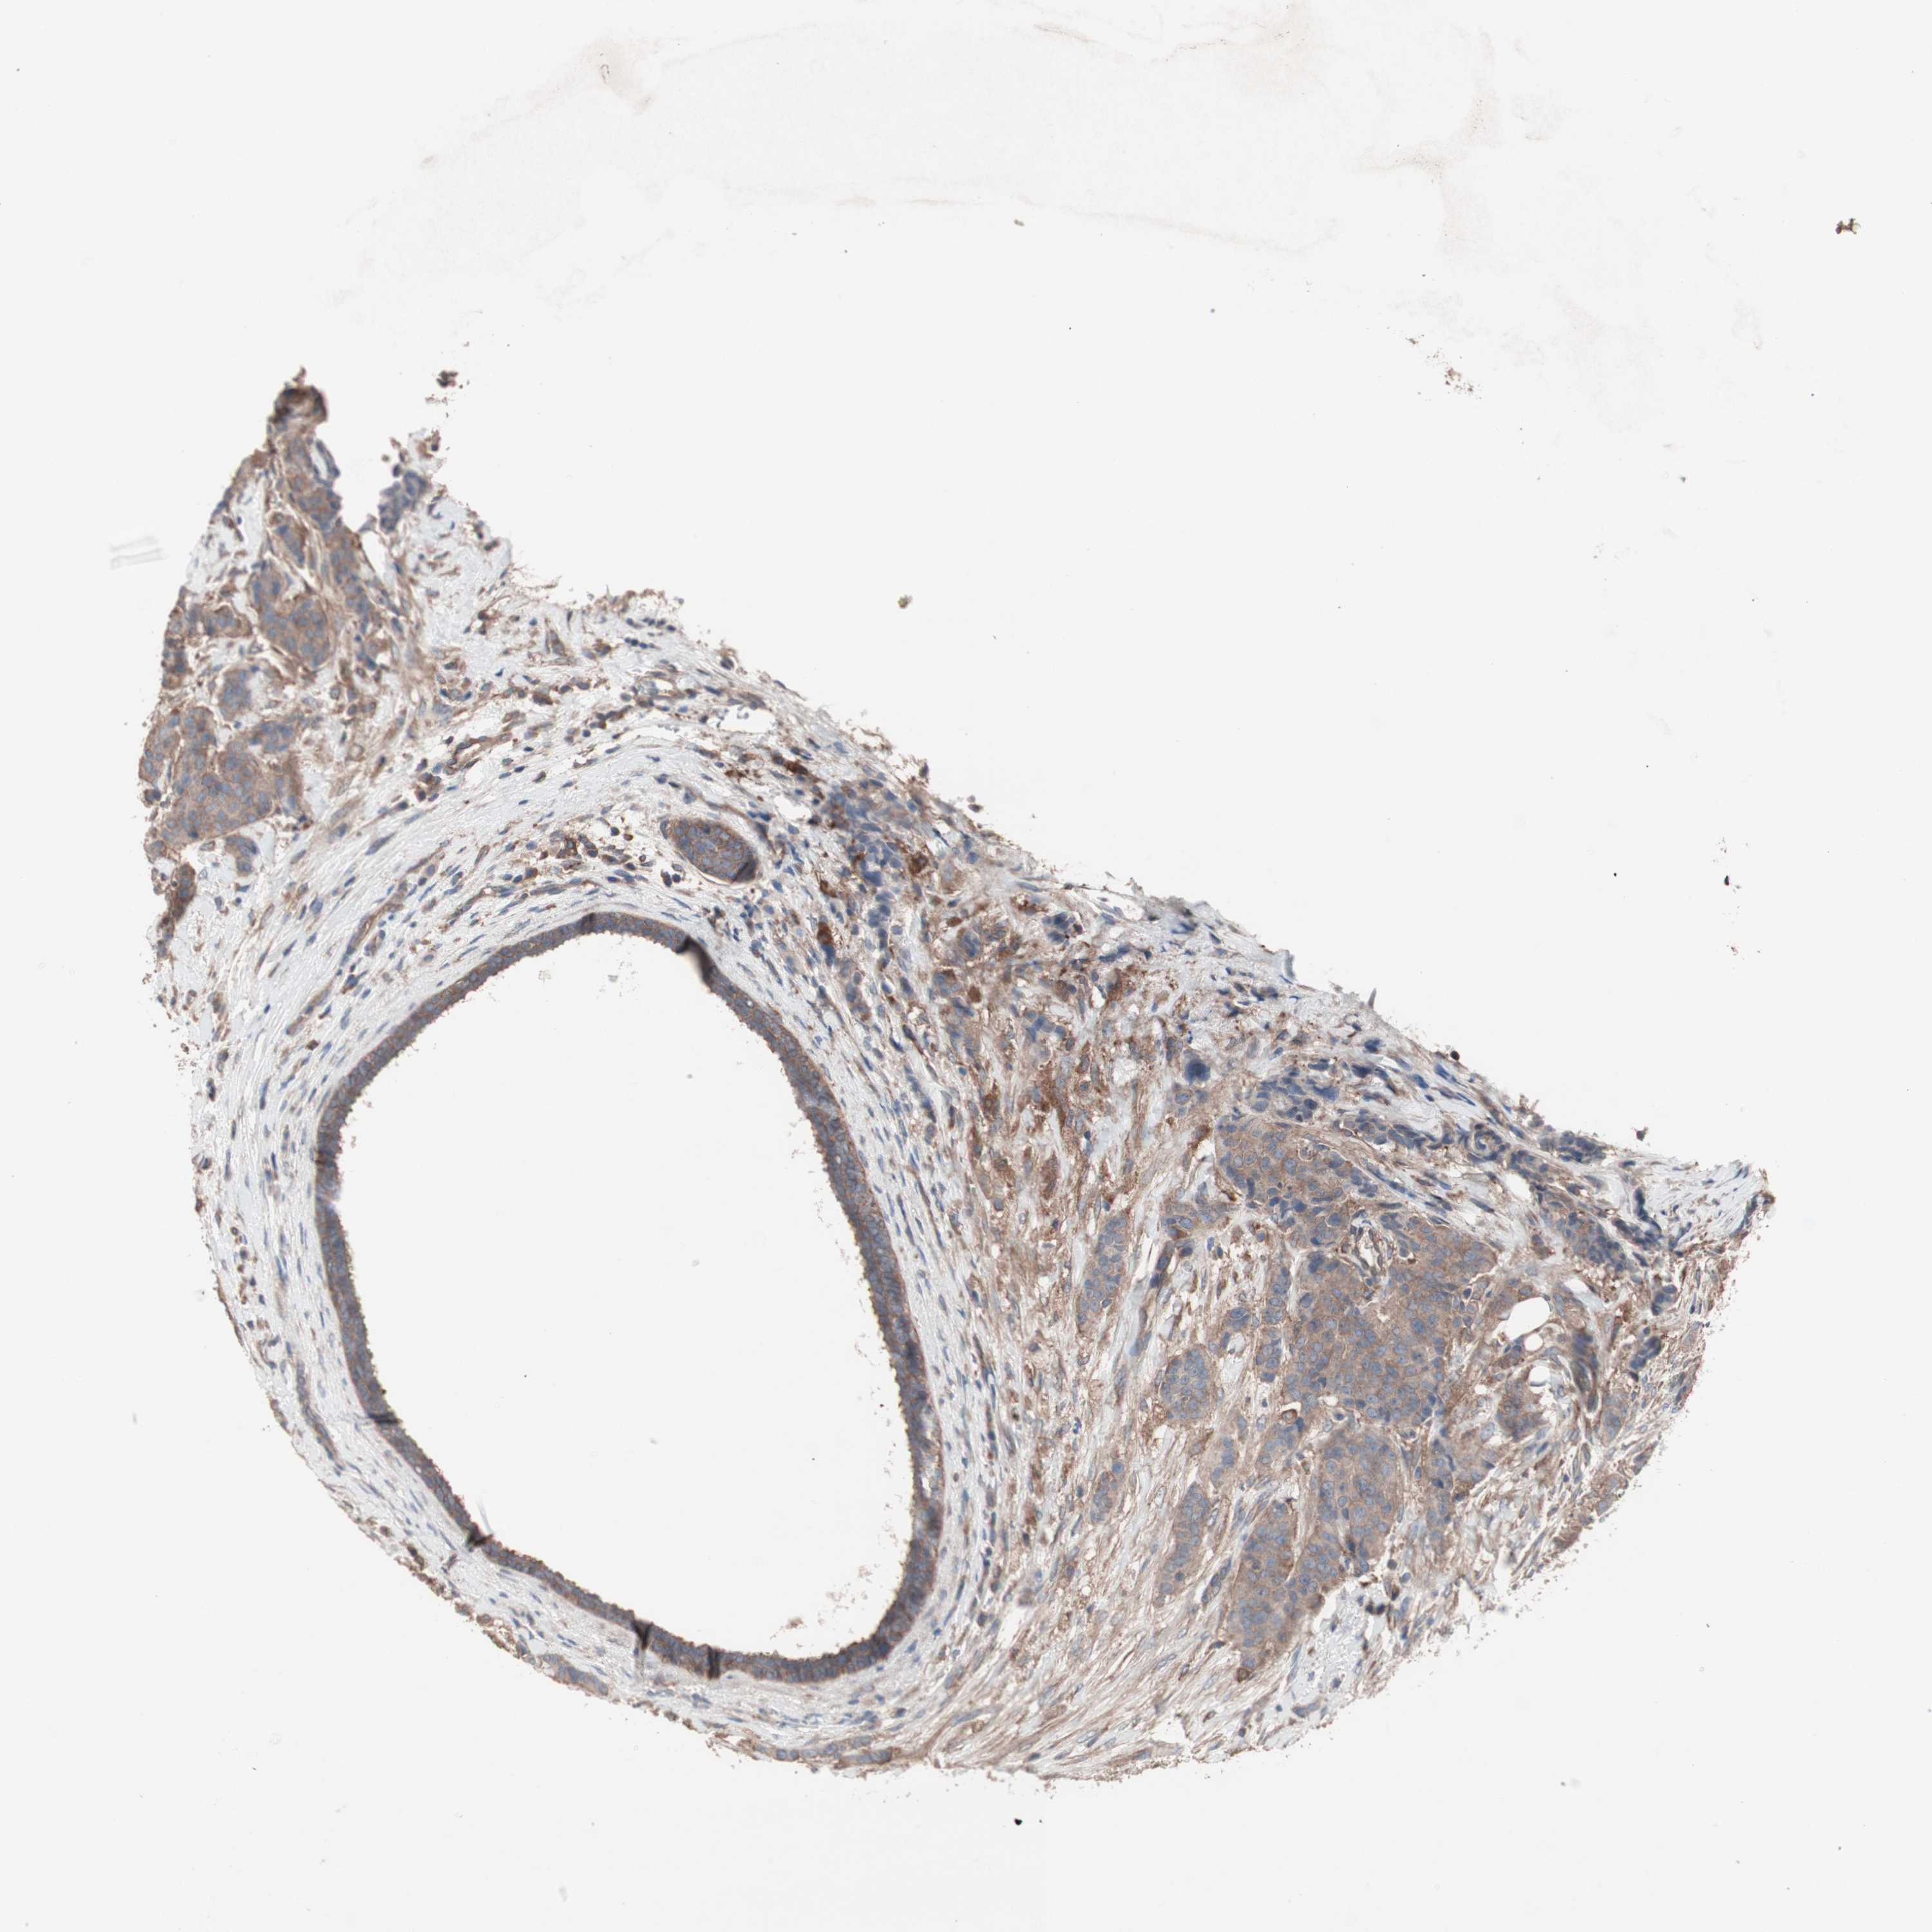

BRCA TCGA BRCA VALIDATION PROTEIN EXPRESSION

ANTIBODIES

AND

VALIDATION